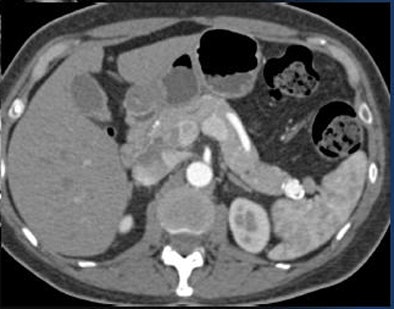

Metastatic tumors of the pancreas, particularly renal cancers, are especially vascular on arterial-phase imaging, but these, too, quickly become isodense, he said.

![]() |

| A renal cell carcinoma metastasis to the pancreas is seen only on arterial-phase CT. |